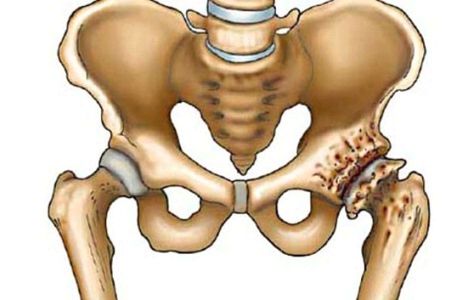

Де знаходяться тазостегнові суглоби (ТБС) не знає, напевно, тільки маленька дитина. Цей суглоб виконує важливі функції в організмі людини. Він витримує вагу здебільшого тіла людини, забезпечує рух, підтримує рівновагу.

Найменші порушення в його функції приносять масу проблем. А вже запалення тазостегнового суглоба, як найбільшого в тілі людини, проявляється особливо гостро і сильно впливає на загальне самопочуття. На жаль, це захворювання досить поширене і зустрічається навіть у дітей. У медицині запальні процеси в суглобах називають артритом, а поразка безпосередньо ТБС називають коксітом.

Біль в області тазостегнового суглоба є основним симптомом запалення